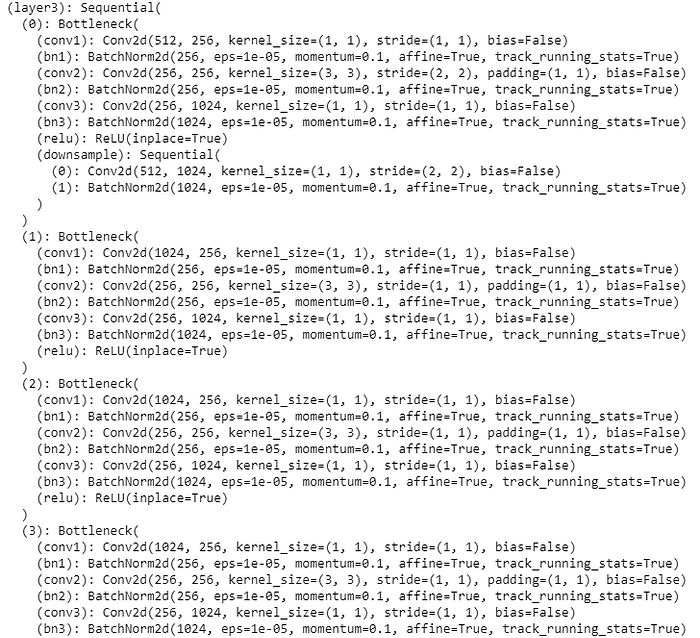

We used ResNet-50 convulational neural network (CNN) in this experiment for deep learning for image recognition and classification. The model layers are as shown below. We used optimizer= ‘Adam’.